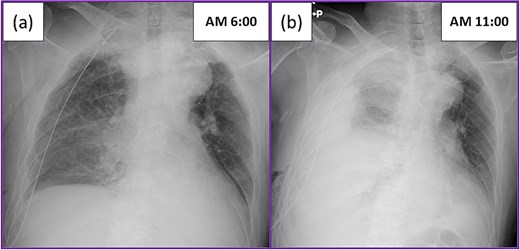

He underwent right lower lobectomy and mediastinal lymph nodes dissection, after non-small cell carcinoma was considered by intraoperative frozen section analysis during a partial resection. The operation was completed uneventfully in 170 minutes, with minimal blood loss (<10 mL). The postoperative course was also uneventful overnight, and blood tests and chest X-ray performed on the morning after surgery did not indicate any abnormalities (Fig. 1a). However, the patient suddenly complained of dyspnea, and a large amount of bloody effusion drained from the chest tube after mobilization. A chest X-ray confirmed the presence of a large amount of effusion (Fig. 1b). Suspecting massive bleeding, we clamped the chest tube and immediately started hyperhydration. However, while the operating room and blood transfusion were being prepared for reoperation, the patient experienced cardiopulmonary arrest following hemorrhagic shock. Bystander cardiopulmonary resuscitation, including tracheal intubation and chest compression, was immediately initiated by the intensive care unit medical staff. Because the operating room was not ready, we decided to perform resuscitative thoracotomy at bedside to apply direct digital pressure.

Postoperative chest X-ray: (a) Chest X-ray on the morning after surgery showed the expected postoperative changes. (b) The patient suddenly complained of dyspnea, and a large amount of bloody effusion drained from the chest tube after mobilization. The chest X-ray showed a large amount of effusion.